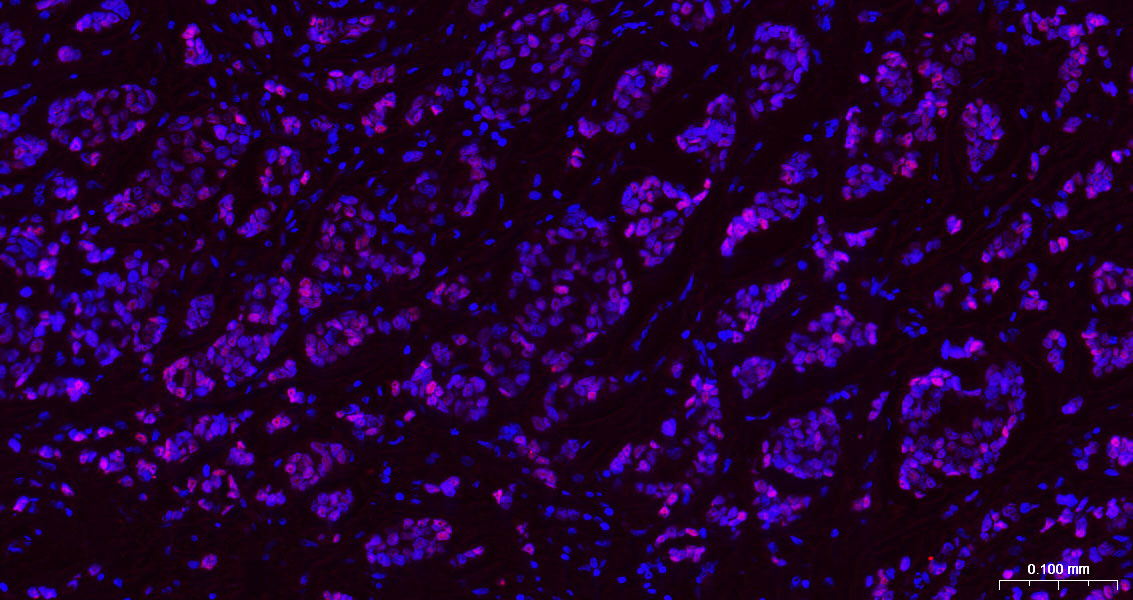

Paraformaldehyde-fixed, paraffin embedded human Breast Cancer; Antigen retrieval by boiling in sodium citrate buffer (pH6.0) for 15 min; The section was incubated with GATA3 Monoclonal Antibody, Unconjugated (bsm-60794R) at 1:200 overnight at 4°C. Followed by conjugated Goat Anti-Rabbit IgG antibody (Rouse Red, bs-0295G-BF647), DAPI (blue, C02-04002) was used to stain the cell nuclei.